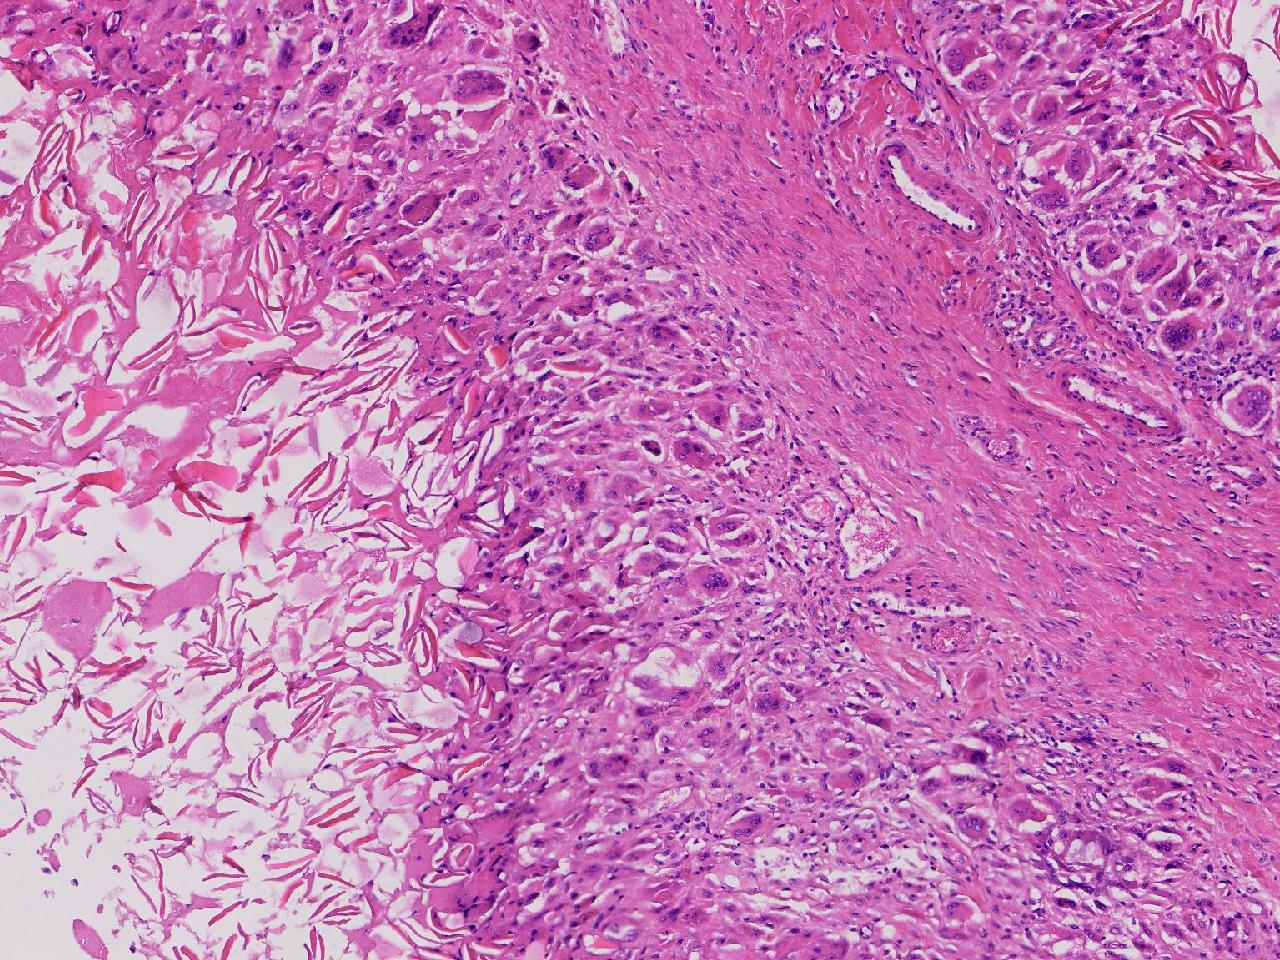

皮样/表皮样囊肿伴周边异物巨细胞反应?

右侧臀部皮下肿物10余年,渐增大,无破溃,无疼痛。

右侧臀部皮下肿物

囊性肿物一个,直径2.5厘米,肿物位于皮下。

异物肉芽肿性炎?

表皮样囊肿伴异物肉芽肿性炎。